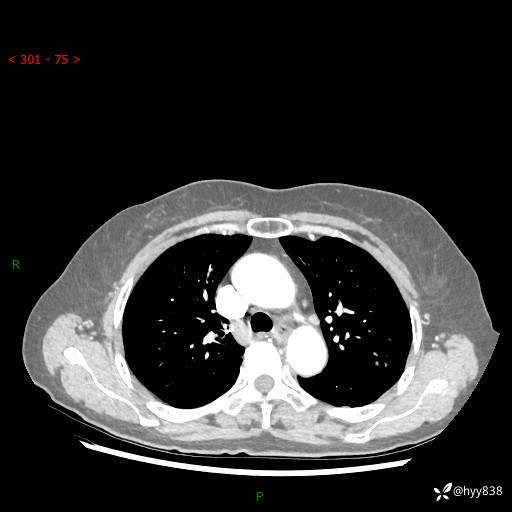

胸部CT增强(2024.8.2)